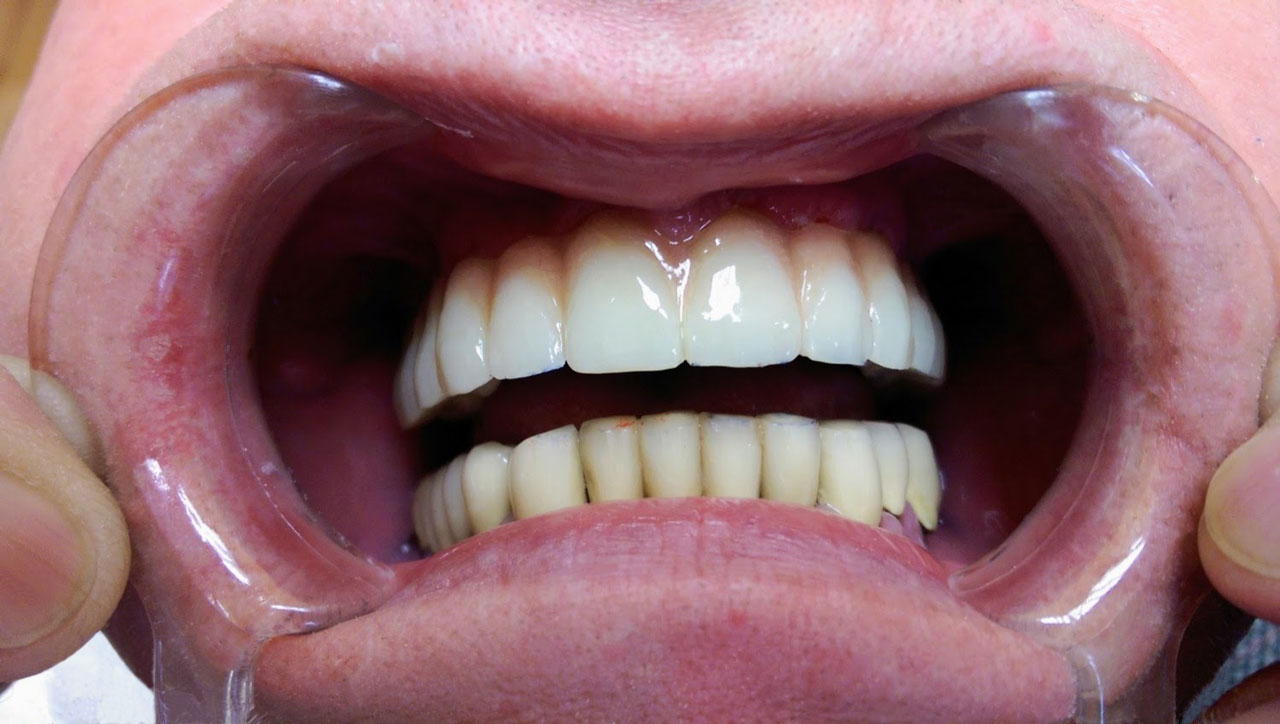

• esettanulmany-12

72 órával az alsó-felső állcsont teljes implantációs helyreállítása után, így mosolyog a páciens a beragasztott, fix hidakkal.